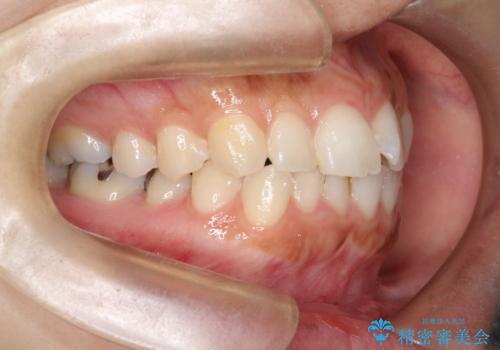

- 口元が出てるのが気になるとのことで来院されました。

上下左右前から4番目の歯を抜歯して前歯を後方に下げて、口元を下げる計画としました。

口元を大きく改善したい場合は抜歯が必要となることが多いです。